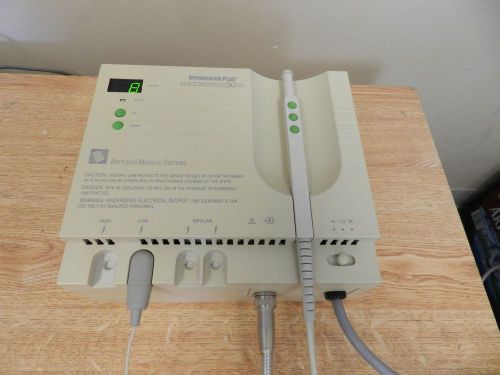

Birtcher Hyfrecator Plus Model 7-797 with Pen